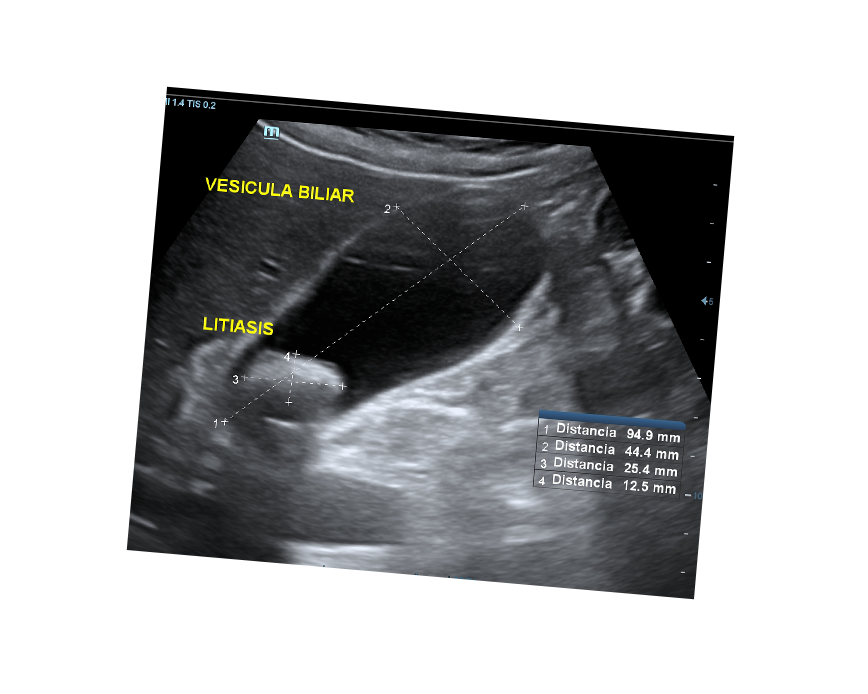

- Estudio de la vesicular biliar y vías biliares